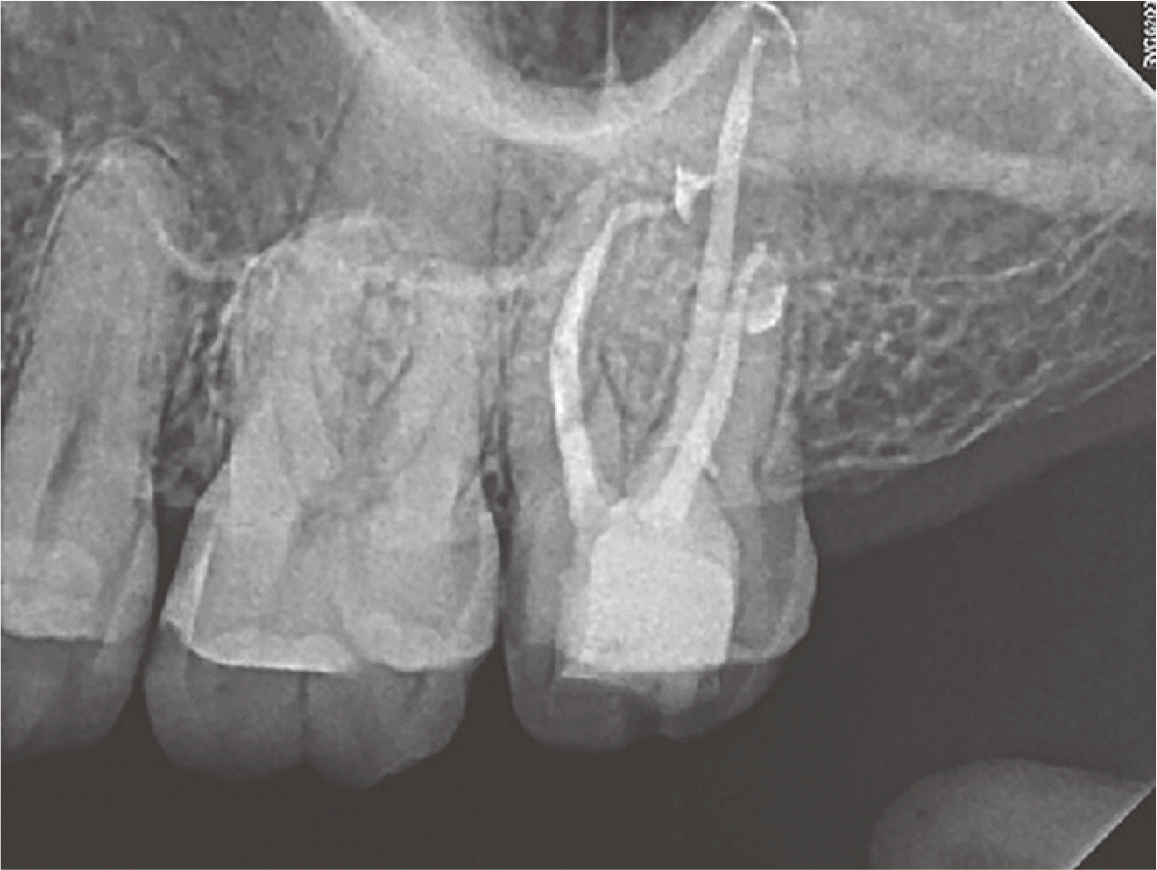

다음 내원시 해당 치아에 대한 타진 및 저작검사에 대한 증상 소실되어 거타퍼차 콘과 AH Plus sealer (Dentsply DeTrey)를 이용한 연속파 근관가압충전으로 마무리 하였고 복합 레진으로 코어 수복후 방사선 사진 촬영하였다(Fig. 2). 한달 반 뒤 재내원 시 환자는 해당치아의 불편감은 처음 내원보다 좋아졌지만 지속적으로 좌측 상악동 부위 먹먹하고 머리가 울리는 느낌이 있다고 하여 이비인후과적 재평가 및 처치를 위해 회신하였다. 이후 이비인후과에서 endoscopic sinus surgery (ESS)를 받았다. Ventilation을 위해서 상악동을 넓혀주고 안에 있는 inflammatory thick serous dicharge를 제거한 다음 상악동내 병변을 관찰하여 큰 이상이 없음을 확인하였고 수술 이후의 비강 점막내 부종과 울혈 가능성을 줄이기 위해 항생제, 소염진통제, 비점막충혈제거제와 진해거담제 등으로 약물치료했다고 한다. 이비인후과의 외래치료 한달 뒤 재내원하였으며 해당 증상 많이 호전되어 골드 크라운 수복 진행하였다(Fig. 3).